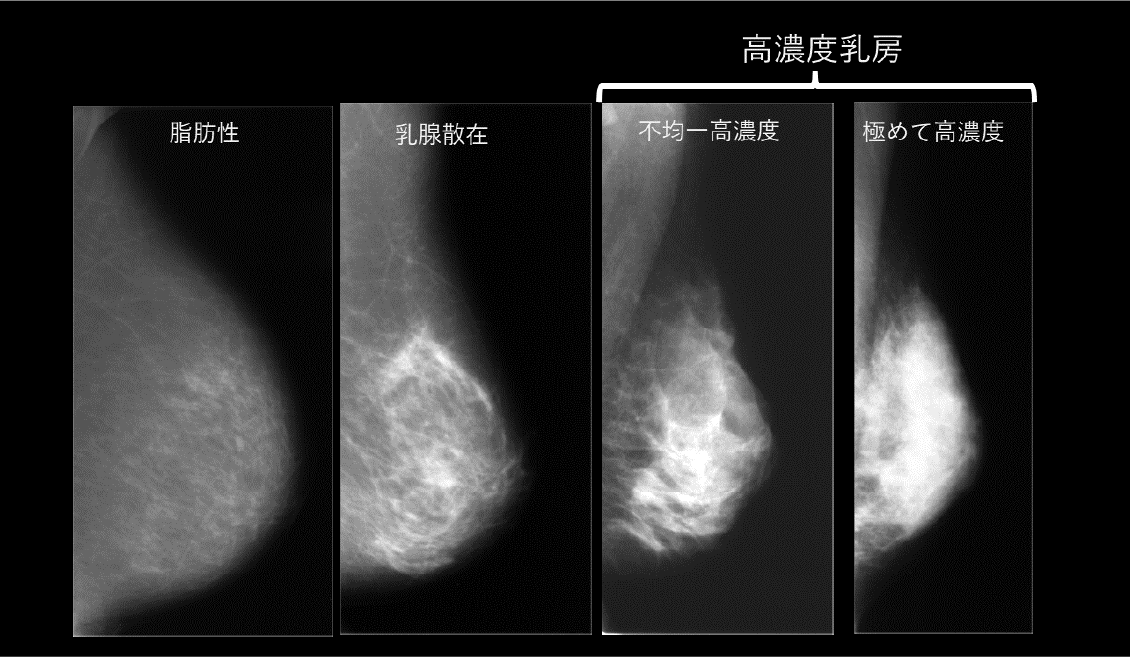

マンモグラフィを行った際、乳房内の乳腺の割合により『見え方』が違います。乳房は、主に乳腺組織と脂肪組織により構成されています。脂肪が多い人はマンモグラフィ検査で乳房全体が黒く写るので、白い塊として写る乳がんのしこりを見つけやすいです。一方、乳腺組織は白く写ります。乳腺組織が多い人のマンモグラフィでは乳房全体が白く写るため、白く写るしこりを見つけにくくなります。このように乳腺組織が多い場合を、「乳腺濃度が高い」と表現します。 乳腺濃度が高い順に「極めて高濃度」「不均一高濃度」「乳腺散在」「脂肪性」の4つのタイプに分かれます。

脂肪がほとんどなく乳腺組織が多い「極めて高濃度」と、乳腺組織の中に脂肪組織が混在している「不均一高濃度」を合わせて「高濃度乳房」と分類します。「高濃度乳房」はマンモグラフィ検査で乳房が白く写り、乳がんが見つけにくくなります。日本人を含むアジアの人は「高濃度乳房」が多いとされています。「高濃度乳房」は特に20歳~閉経前の方には多くみられます。自分の乳房がどのタイプかはマンモグラフィを見ることで分かります。乳房の大きさや硬さでは判断できません。検診などの機会に確認しておきましょう。また「高濃度乳房」だからといって、将来必ず乳がんになることではありません。過度に心配をしないよう、医師と相談することが重要です。